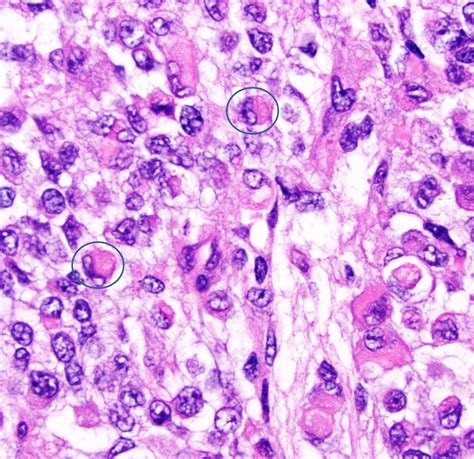

The term Atypical Teratoid Tumor, often referred to as AT/RT, describes a tumor that is composed of various types of cells, often resembling both embryonic tissues and rhabdoid cells (cells that resemble muscle). A defining feature of these tumors is a specific genetic mutation involving the SMARCB1 (also known as INI1) or, more rarely, the SMARCA4 gene. These genes act as tumor suppressors, and when they are dysfunctional, cells can grow uncontrollably.

Diagnosis typically begins with advanced neuroimaging, such as MRI scans with and without contrast, to visualize the tumor's size and location. However, imaging alone is rarely sufficient. A definitive diagnosis is achieved through a surgical biopsy or total resection, followed by a rigorous pathological examination. Pathologists look for the loss of INI1 protein expression in the tumor cells, which serves as a molecular hallmark for an Atypical Teratoid Tumor.

• Atypical Teratoid Rhabdoid Tumor Histology